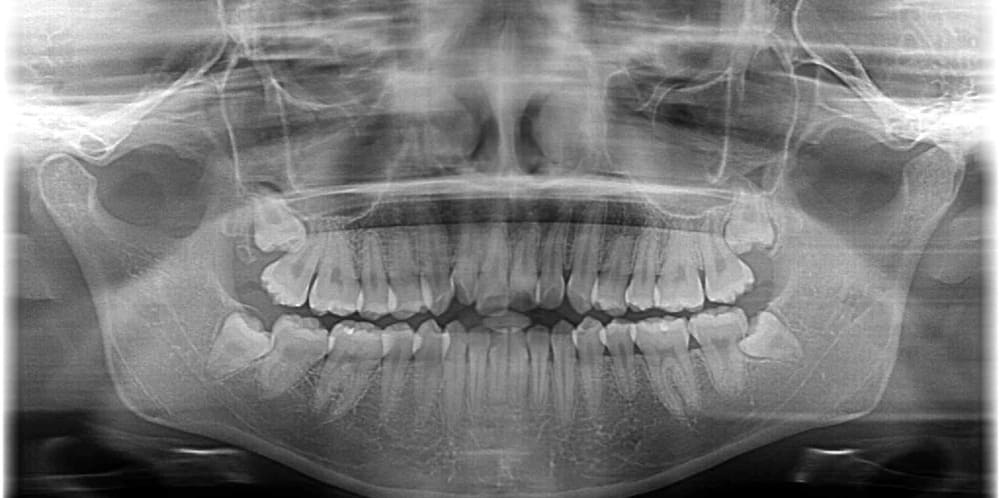

パノラマレントゲン写真です。

上下左右の親知らずの埋伏が認められます。

矯正治療中にタイミングを見てすべて抜去する予定です。

※親知らずの抜歯は保険適用になるので大学病院を紹介させていただき、抜歯を行うことが多いです。

パノラマレントゲン写真です。親知らずは、4本とも抜歯されています。